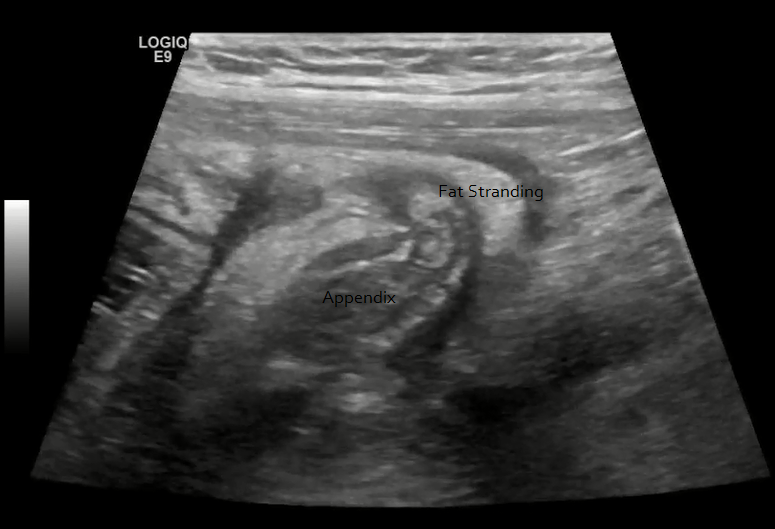

Appendix Ultrasound